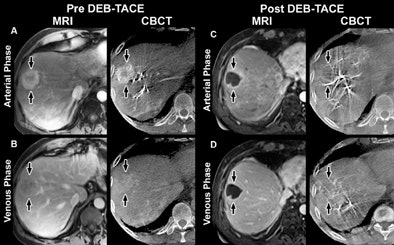

| Images show arterial- and venous-phase MRI and CBCT in a 58-year-old man with HCC in right lobe secondary to hepatitis C virus. MR images were acquired one month before and one month after TACE using doxorubicin-eluting beads; CBCT was acquired before and immediately after TACE. (A) Arterial-phase images obtained before TACE. MR image shows a 32-mm mass in right lobe with 75% enhancement. CBCT shows mass with similar enhancement (80%). (B) Venous-phase images obtained before TACE. MR image shows mass with partial washout (50% enhancement). CBCT shows mass with almost the same decrease in enhancement (65%). (C) Arterial-phase images obtained after TACE. MR image shows mass with almost no enhancement (5%); tumor size remains unchanged (31 mm). CBCT shows intraprocedural mass enhancement decreased by 100%, which allowed prediction of objective EASL response at one month. (D) Venous-phase images obtained after TACE. MR shows mass with almost no enhancement (5%). Conebeam CT scan shows intraprocedural mass enhancement decreased by 92%, which allowed prediction of an objective EASL response at one month. Images republished with permission of the RSNA from Loffroy et al, Radiology, November 9, 2012. |

One-month follow-up imaging with MR showed complete or partial tumor response in 74% of lesions on the arterial phase and 76% in the venous phase, the study team reported. Paired t-test analysis showed significant reduction in tumor enhancement in both modalities (p < 0.001).

The volume enhancement reductions correlated linearly with MR findings, with high estimated correlations for first (k = 0.89) and second (k = 0.82) phases. In addition, multilogistic regression showed a significant relationship between CBCT tumor enhancement after TACE and complete or partial tumor response at MR for arterial and venous phases. The radiation dose for dual-phase, as measured in a piglet model, was 3.08 mSv.